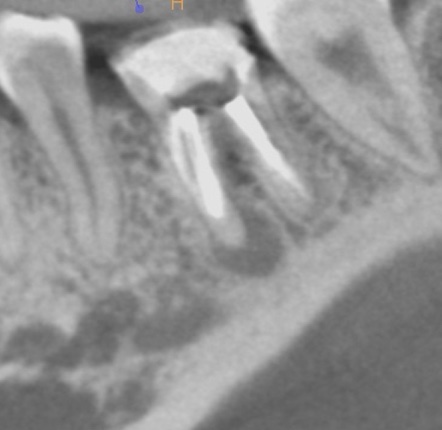

一年後